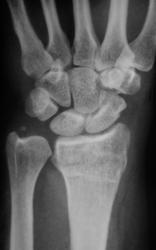

Пол пациента: Мужской пол Тип патологии: Травма Область исследования: Скелетно-мышечная система Методы исследования: Rg Травма. Пациент направлен врачом хирургом на рентгенографию лучезапястного сустава. Произведено исследование. Ваше мнение коллеги? Thu, 15/10/2009 - 21:47 #1 Наталия Offline Last seen: 8 years 8 months ago Joined: 30.07.2008 - 13:24 Posts: 538 Откол части шиловидного отростка локтевой кости, перелом лучевой кости в питичном месте, перелом ладьевидной кости. Может отрыв крючка. Thu, 15/10/2009 - 22:25 #2 v1tal Offline Last seen: 4 years 10 months ago Joined: 07.06.2008 - 19:41 Posts: 1779 Можно добавить краевой перелом кости-трапеции. "Знаешь, у некоторых врачей есть комплекс мессии — им необходимо спасать мир. А у тебя комплекс Рубика — тебе необходимо решать головоломки." Sun, 18/10/2009 - 23:33 #3 Катенёв Валенти... Offline Last seen: 7 years 1 month ago Joined: 22.03.2008 - 22:15 Posts: 54876 Так выходит - 3 перелома!? Mon, 19/10/2009 - 20:15 #4 Анатолий Владим... Offline Last seen: 7 years 11 months ago Joined: 16.10.2009 - 21:16 Posts: 1941 В ладьевидной кости в норме часто можно наблюдать ступеньку по наружному контуру, которая симулирует перелом. Для окончательного решения вопроса необходима рентгенограмма костей запястья в косой проекции.

Откол части шиловидного отростка локтевой кости, перелом лучевой кости в питичном месте, перелом ладьевидной кости. Может отрыв крючка.

Можно добавить краевой перелом кости-трапеции.

Так выходит - 3 перелома!?

В ладьевидной кости в норме часто можно наблюдать ступеньку по наружному контуру, которая симулирует перелом. Для окончательного решения вопроса необходима рентгенограмма костей запястья в косой проекции.